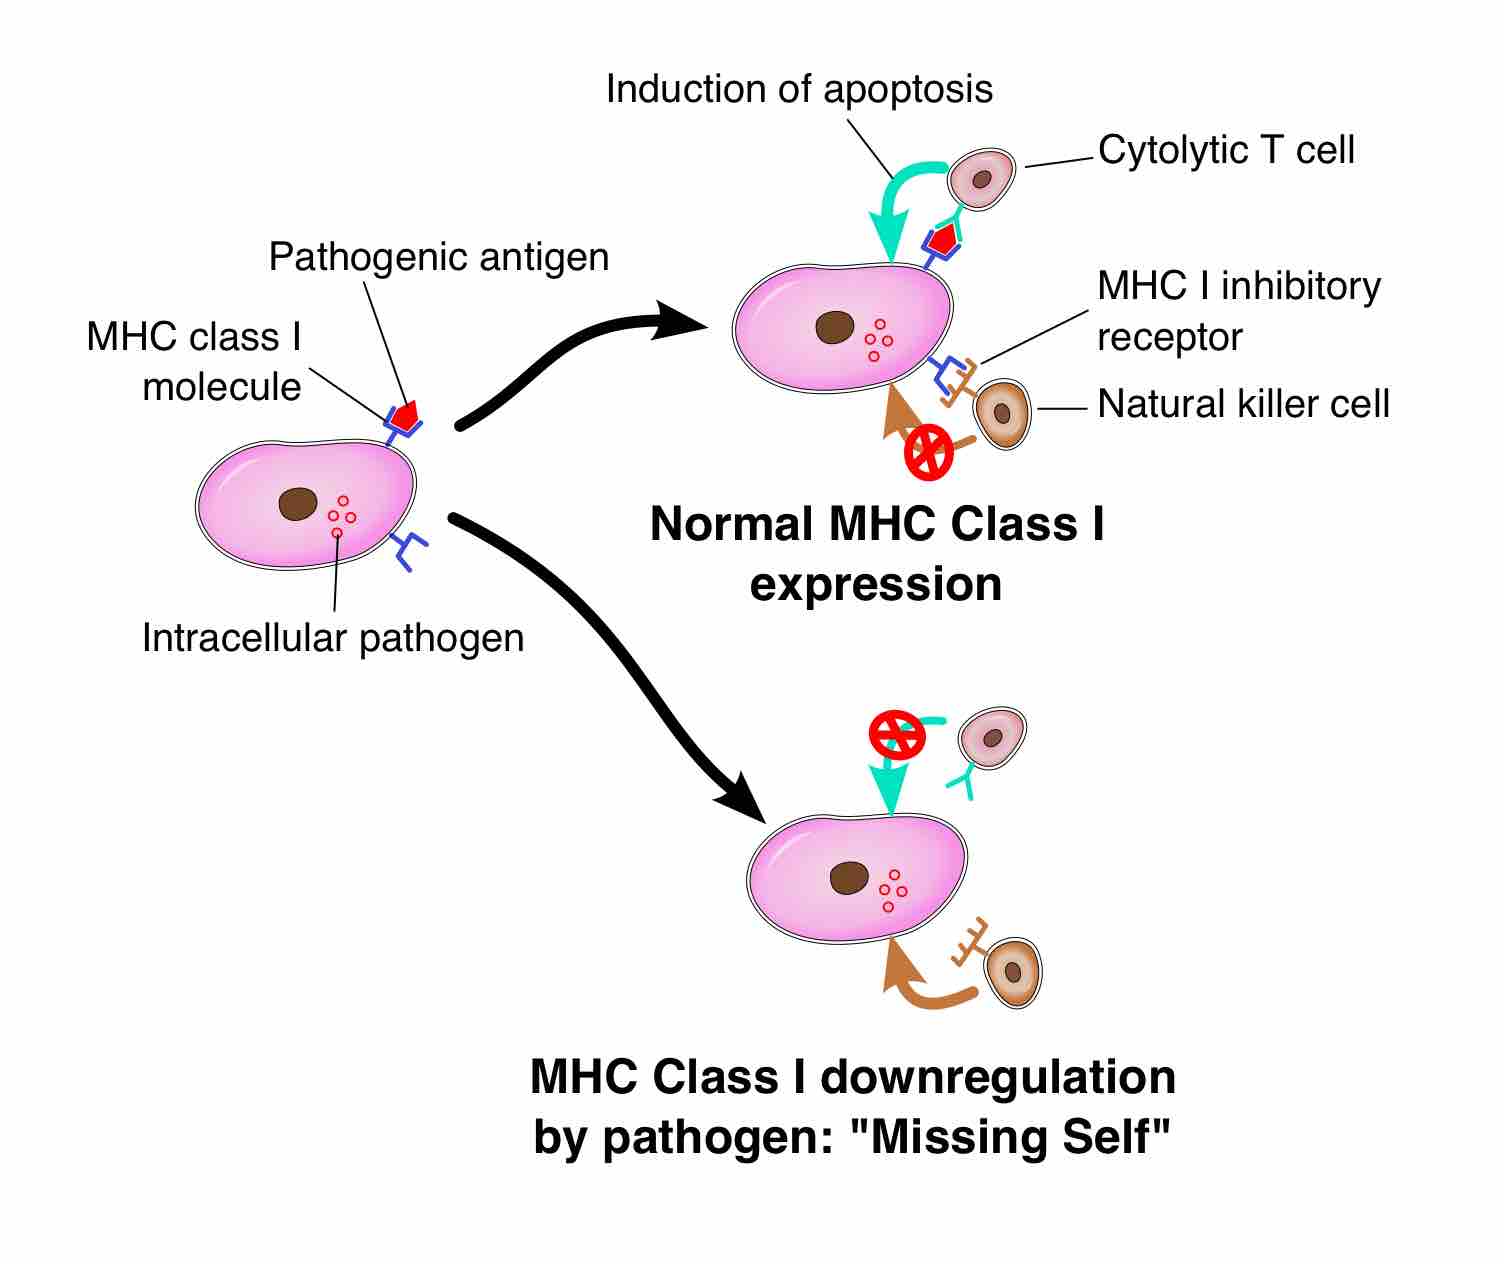

Natural killer cells are part of the innate immune response that recognize abnormal MHC I molecules on infected/tumor cells and kill them.

Natural killer cells (or NK cells) are a type of cytotoxic lymphocyte critical to the innate immune system.

Cell-mediated immunity involves cytotoxic T cells recognizing infected cells and bringing about their destruction.